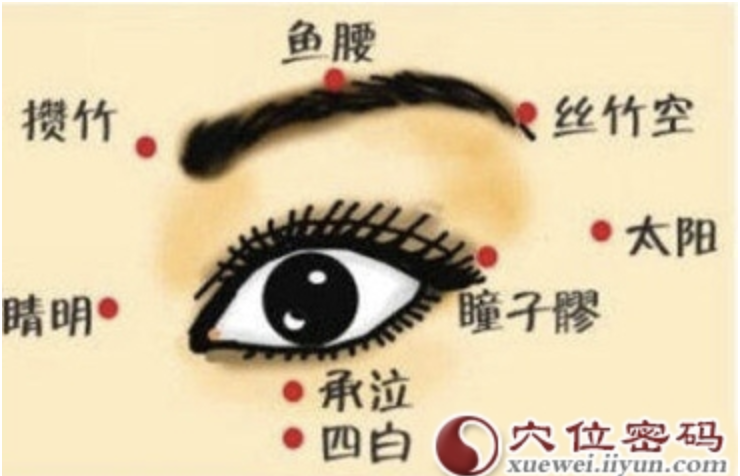

鱼腰

【定位】 在额部,瞳孔直上,眉毛正中。

【主治】 目赤肿痛,目翳,眼睑瞤(rún)动,眼睑下垂,眶上神经痛。

【刺灸法】 平刺 0.3 ~ 0.5 寸;紧灸。